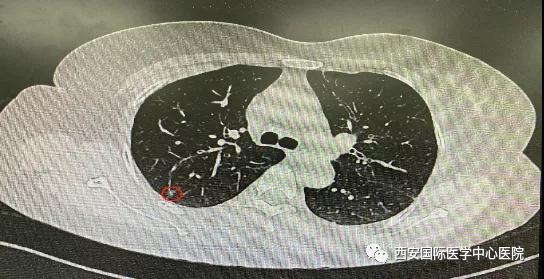

日前,西安國際醫(yī)學中心醫(yī)院胸科醫(yī)院胸外科二病區(qū)成功開展LungPro全肺導航下經(jīng)支氣管鏡注入亞甲藍染色劑標記結(jié)節(jié)位置,行精準肺段切除術(shù),成為西北地區(qū)首例“Lung Pro全肺診療導航系統(tǒng)聯(lián)合單孔胸腔鏡下右肺上葉后段切除術(shù)”,填補了西北地……